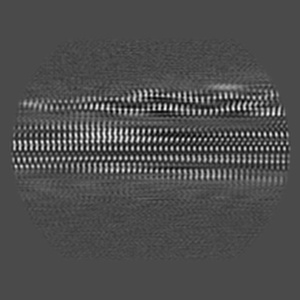

P301S Tau Filaments from the Brains of Tg2541 Transgenic Mouse Line

Helical reconstruction

3.09 Å

Sample: P301S Tau Protein Filament (Tg2541)

Cryo-EM structures of tau filaments from the brains of mice transgenic for human mutant P301S Tau.

Schweighauser M, Murzin AG, Macdonald J, Lavenir I, Crowther RA, Scheres SHW, Goedert M

(2023) Acta Neuropathol , 11 , 160 - 160